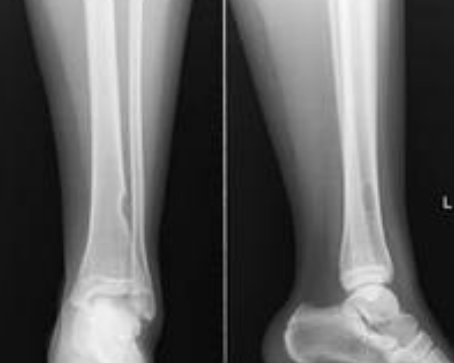

骨癌片子

骨癌ct图片